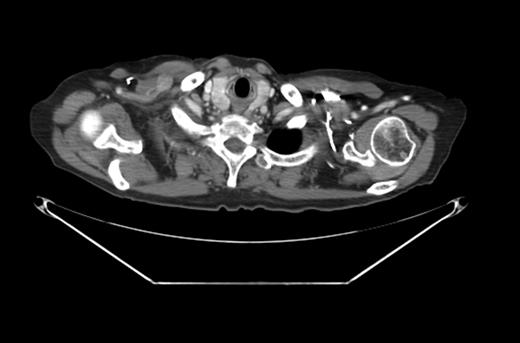

A PET-CT was performed, which demonstrated a round enhancing 1.8 × 1.5 cm right subpectoral lymph node with FDG uptake and a maximum SUV of 4.0 suspicious for metastatic disease (Figs 1 and 2). Additionally, an incidental 4.1 × 3.4 cm mass within the midpole of the left kidney was heterogeneously enhancing with increased FDG uptake and a maximum SUV of 8.6 suspicious for a renal cell carcinoma or less likely a transitional cell carcinoma (Figs 3 and 4).